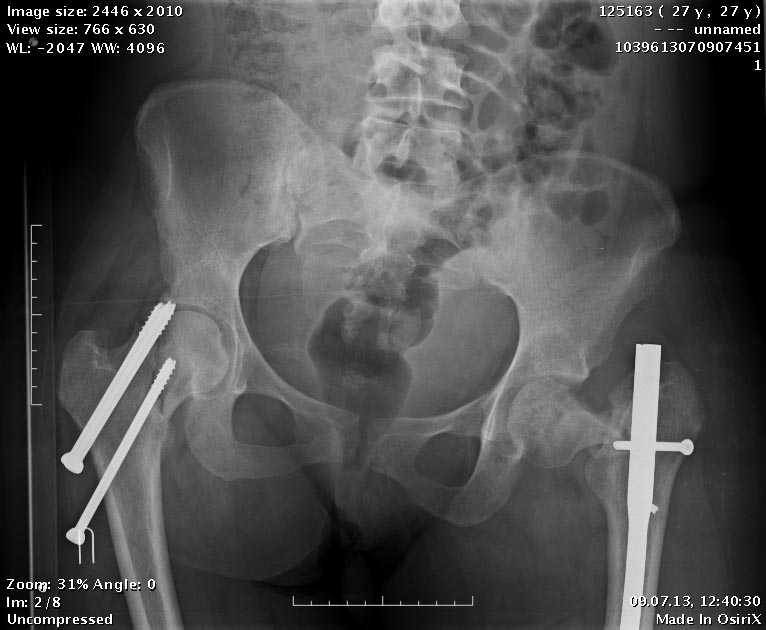

Продолжение истории, начало см.http://weborto.net/forum/1370513039/.

Сегодня сделали левое бедро. Сделана аналогичная чрескожная

вальгизирующая остеотомия, закрытый интрамедуллярный остеосинтез

Affixus.  Длинным, с учетом еще и бывшего диафизарного перелома. Были

какие-то мысли насчет пластики дефекта шейки - решили воздержаться.